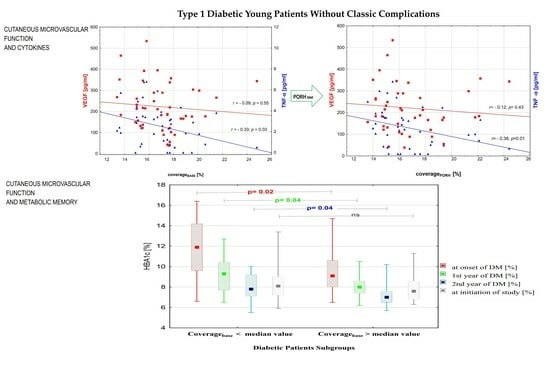

3.1. Subgroup Comparison

3.2. Correlations between Variables

| HBA1c at onset of DM [%] | 9.9 (6.5–16.4) | 11.8 (6.6–16.4) | 9.1 (6.5–14.7) | 0.02 |

| HBA1c 1st year of DM [%] | 8.2 (6.2–12.7) | 9.3 (6.5–12.7) | 7.90 (6.2–10.5) | 0.04 |

| HBA1c 2nd year of DM [%] | 7.35 (5.5–10.4) | 7.8 (5.5–10) | 7.00 (5.7–10.4) | 0.04 |

| HBA1c at initiation of study [%] | 8.1 (5.9–13.4) | 8.1 (5.9–13.4) | 8.0 (6.3–11.8) | 0.44 |

| TNF-α [pg/mL] | 2.4 (0–6.78) | 3.4 (0–6.8) | 1.25 (0–4.3) | 0.001 |

| VEGF [pg/mL] | 211.75 (38.8–533.73) | 232.2 (120.4–533.7) | 176.8 (38.81–357.4) | 0.03 |